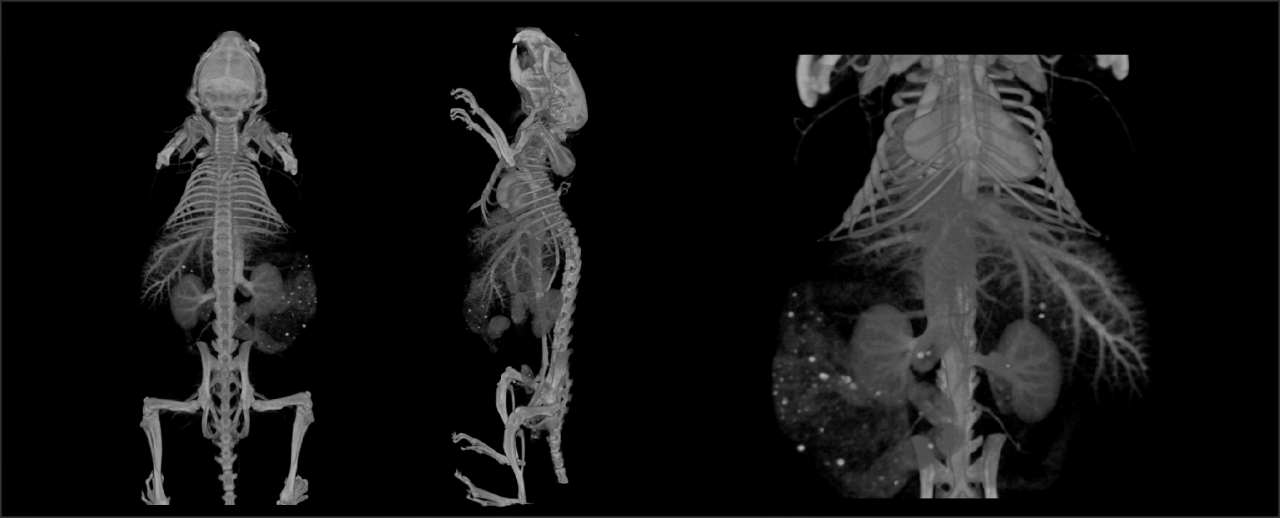

Range of CT only Applications: Rabbits

Range of CT only Applications:

Obese Mouse Contrast

Enhanced CT